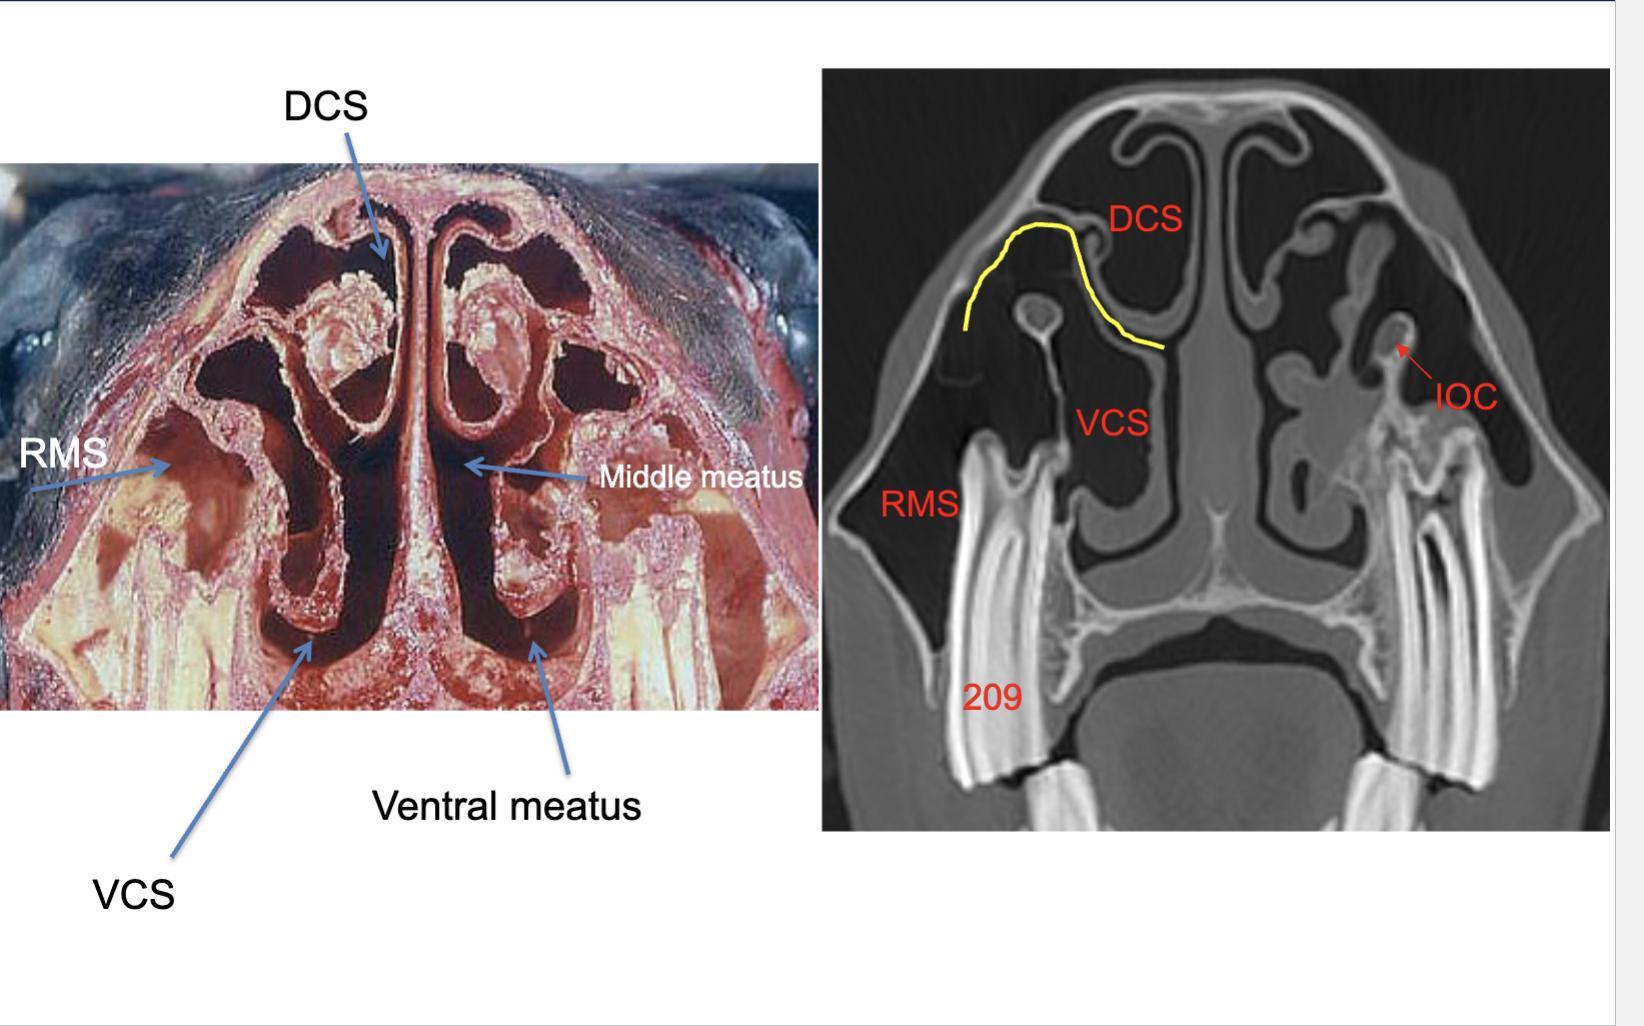

What are the groups and names of the paranasal sinuses?

Rostral group (2 sinuses)

Rostral maxillary (RMS)

Ventral conchal (VCS)

Caudal group (5 sinuses)

Caudal maxillary (CMS)

Frontal (FS)

Dorsal conchal (DCS)

Sphenopalatine (SP)

Ethmoid sinus (ES)

Describe the anatomy of the dorsal and ventral conchae

Thin scrolls of cartilage and bone

Divide nasal passage into 3 meati:

Dorsal

Middle

Ventral

Form conchal sinuses caudally